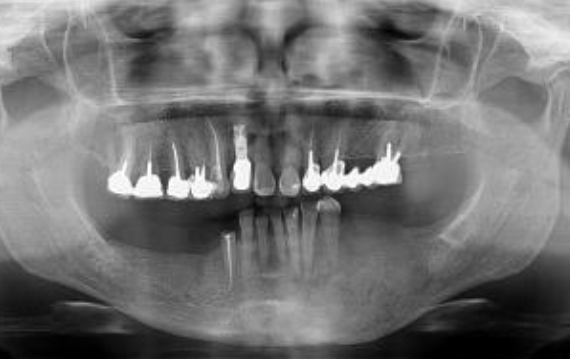

Odontogenic keratocyst (OKC)

Developmental/odontogenic RL lesions

well defined RL

smooth borders, scalloping may occur between roots

can be uni or multiocular

strong preference for posterior mandible

high recurrence rate